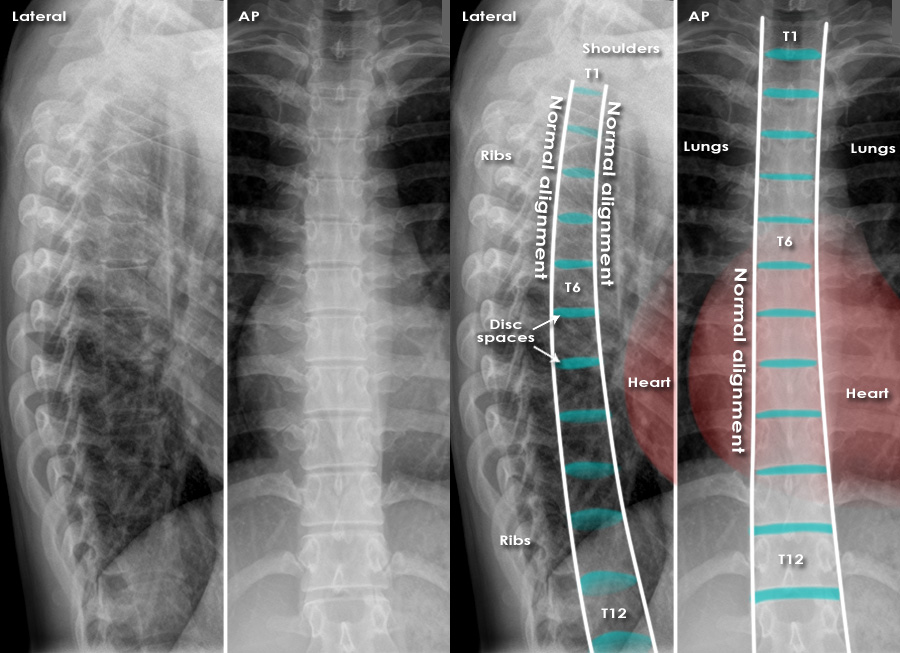

Измерение кифоза грудного отдела: Рентгеновские снимки